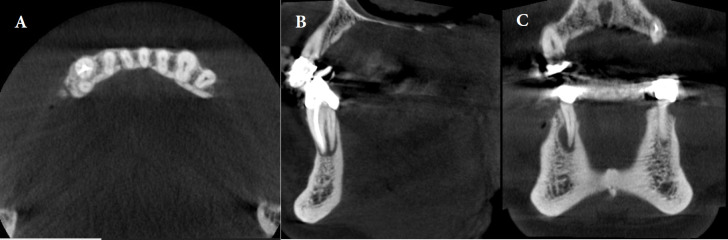

Results: Of the 2053 teeth examined, 14.9% had at least one untreated canal. Untreated canals in teeth increase the chance of having a periapical lesion, raising the prevalence by 11 times. Of these, 91.8% had both untreated canals and periapical lesions. This was more than teeth without untreated canals (35.8%). Most untreated canals were in maxillary molars (65.3%), and mandibular molars (12.54%). There was a statistically significant relationship (P<0.001) between the number of roots, canals, expansion, destruction, and jaw type with the prevalence of untreated canals. The maxillary first molar (68.66%) and second mesiobuccal (MB2) canal (63.27%) had the highest percentages of untreated canals.

Conclusions: The MB2 had the highest prevalence of untreated canals. The presence of untreated canals significantly increased the risk of expansion and/or destruction. Therefore, identifying these conditions can also be useful in diagnosing untreated canals. Dentists should assess the anatomy of the tooth and the structure of the root canal to minimize the possibility of an untreated canal. CBCT can assist in this process.